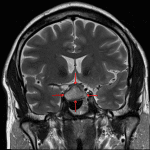

- Peripherally-enhancing sellar/suprasellar mass measuring 2.5 x 1.6 x 1.7 cm, which is not separable from the pituitary gland

- Centrally, the lesion is mildly T1 hypointense and T2 hyperintense

- The lesion bulges to the intercarotid line on the right and remains medial to the medial carotid tangent line on the left

- The lesion contacts and mildly uplifts the optic chiasm

Cystic pituitary adenoma